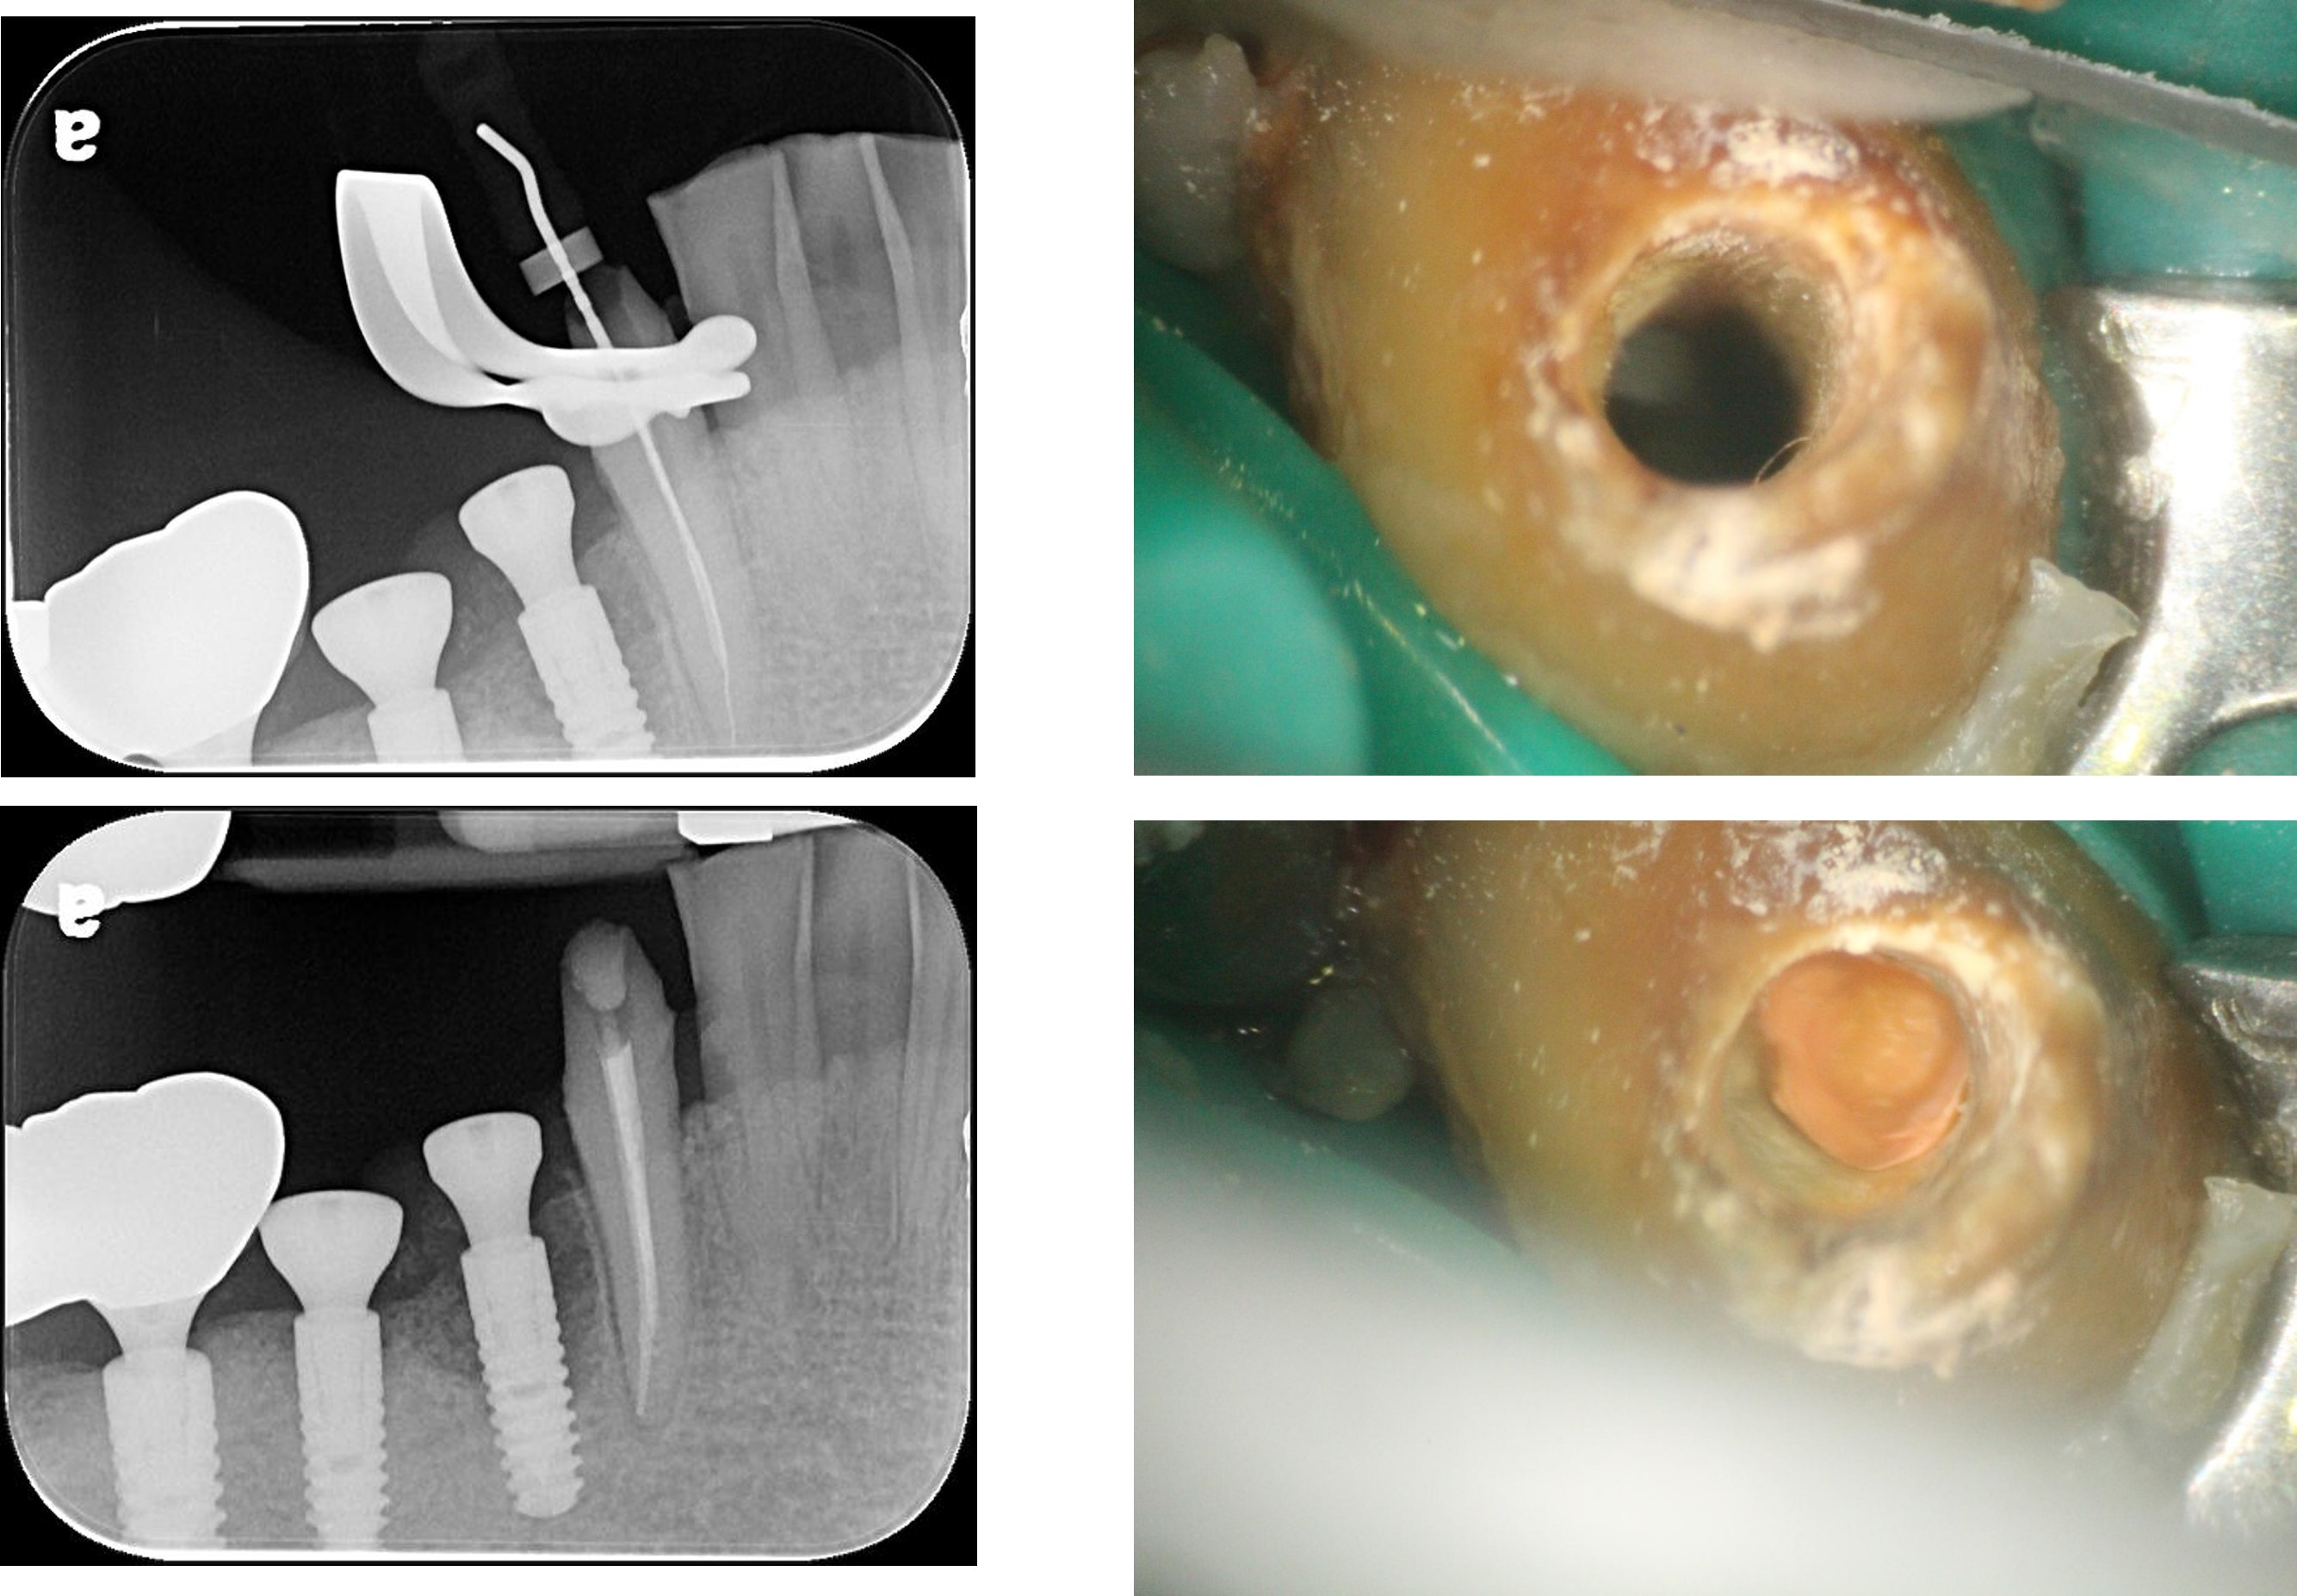

顯微根管治療:#43